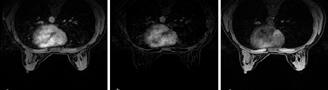

Figura 1. Pacient de 57ani cu simptomatologie acută sugestivă pentru AVC ischemic acut: CT -ul nativ nu a decelat elemente de semiologie sugestive pentru AVC ischemic acut (A), însă secvențele IRM au evidențiat o arie în hipersemnal FLAIR (B) și cu restricție de difuzie (C) localizată occipital paramedian dreapta, sugestivă pentru AVC ischemic acut (Spitalul Clinic de Urgență „Prof. N. Oblu“, Iași)

În contrast, imagistica prin rezonanță magnetică, în special secvențele de difuzie, oferă o sensibilitate superioară pentru detectarea precoce a infarctului ischemic,

fiind capabilă să identifice modificări la nivel celular la doar câteva minute după debutul simptomelor (Figura 1) (Mouridsen et al., 2020), (Nukovic et al., 2023). De asemenea, IRM este capabilă să ofere o evaluare superioară a integrității parenchimului cerebral, a viabilității țesutului și a extinderii leziunii ischemice, facilitând o caracterizare mai detaliată a AVC-ului ischemic (Cortés-Albornoz et al., 2025).